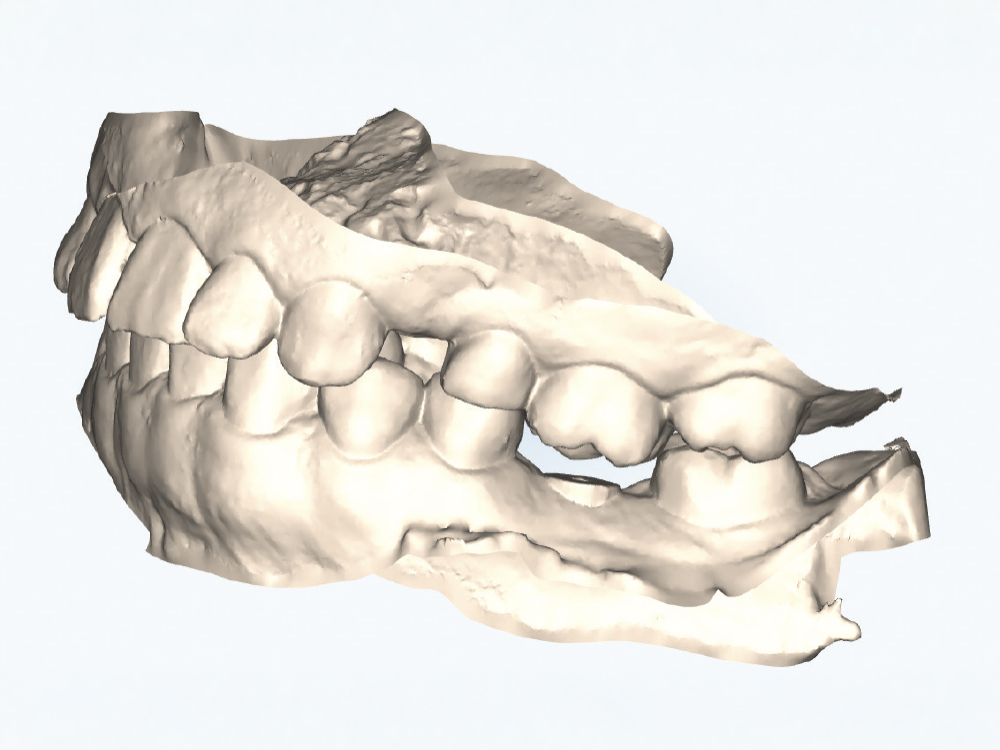

Implant post scan on left side of mouth

Implant post scan pointing down

Implant post scan close up

Verify the Scans Before Dismissing the Patient. Review all critical areas while the patient is still in the chair, ensuring complete scan body capture, accurate contacts, adequate tissue detail, and proper bite registration. Zoom in on critical areas to verify resolution and completeness. It takes only two minutes to verify a scan, but potentially days before a patient is able to return to your practice. Use the scanner’s analysis tools to identify distortions or artifacts.

Don’t Trust Your Scan Without Verification. Screen visualization during scanning does not guarantee complete data capture, and small gaps, artifacts, or distortions may not be evident during active scanning. Discovering scan deficiencies after the patient leaves wastes everyone’s time. Make verification a non-negotiable final step at every scanning appointment.